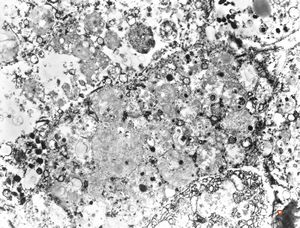

F,69y. | urinary bladder - malakoplakia